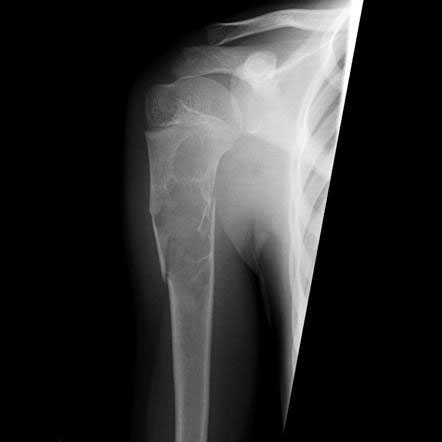

Опухоли костей являются редкими поражениями. Большая часть таких опухолей - доброкачественные образования, которые часто обнаруживаются случайно при радиологических исследованиях, проводимых по другим причинам. Что касается жалоб, они обычно проявляются отеком и болью. В редких случаях они обнаруживаются вследствие вызванного ими перелома в месте их расположения. Наиболее часто встречающимися доброкачественными образованиями являются остеоид-остеома, остеохондрома (экзостоз), энхондрома, неоссифицирующая фиброма, эозинофильная гранулема, простая костная киста, фиброзная дисплазия и внутрикостная липома / ганглия.